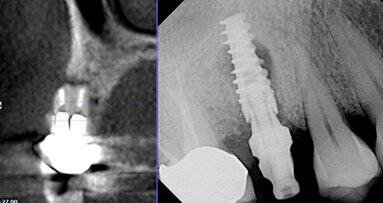

The GXCB-500 HD has a unique, adjustable 3-D medium field of view that can be sized from as large as 8 x 14 cm to as small as 2 x 8 cm. This allows for the greatest flexibility of treatment covering a host of procedures from TMJ to implants to endo.